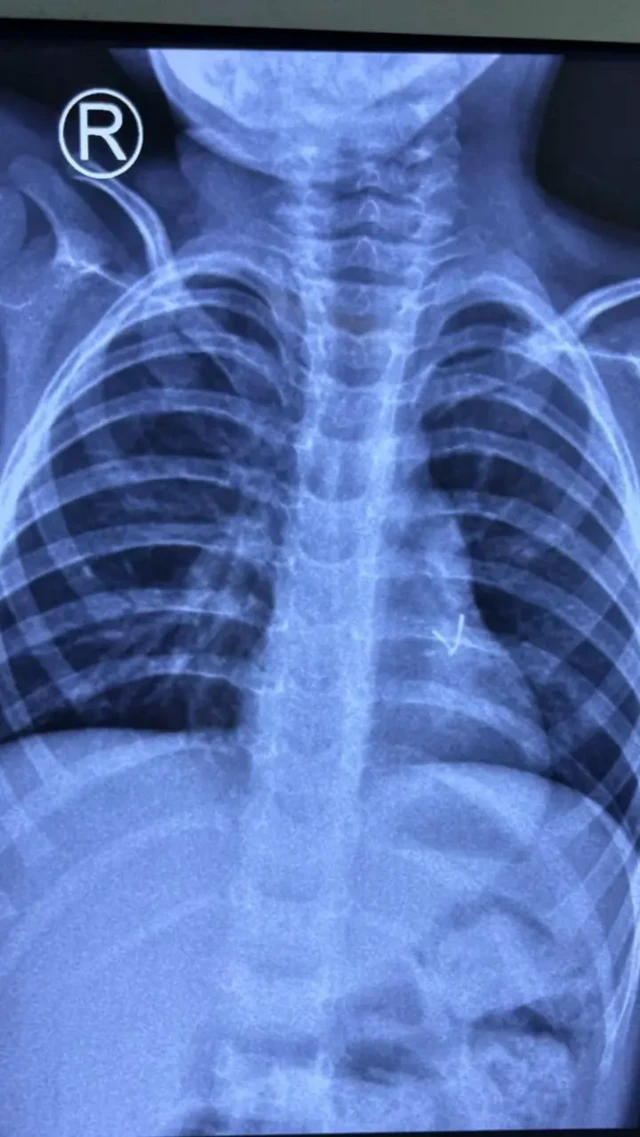

تفصیلی جسمانی معائنے کی ابتدائی رپورٹ میں بچے کے ایک پھیپھڑے کے بائیں جانب دھات کا ایک ٹکڑا نظر آیا جسے بذریعہ آپریشن نکالنے کا فیصلہ کیا گیا۔

ڈاکٹروں نے تین سالہ بچے کے پھیپھڑے میں پھنسے دھاتی ایل ای ڈی بلب کو کامیاب آپریشن کی مدد سے نکال دیا۔

ڈاکٹرز کو راہل کے پھیپھڑوں سے ایل ای ڈی بلب نکالنے کے لیے اُن کے جسم پر چار سینٹی میٹر کا کٹ لگانا پڑا۔ ڈاکٹروں نے کھلونا کار کا ایل ای ڈی بلب نکالنے کا کامیاب آپریشن کیا جس کے بعد بچے کے پھیپھڑوں نے مکمل کام کرنا شروع کیا۔

اس آپریشن میں حصہ لینے والے سرجن ڈاکٹر ویمیش راجپوت نے کہا کہ ’یہ بہت ہی نایاب کیس تھا جس سے ہم نے ڈیل کیا۔ چھوٹا ایل ای ڈی بلب پھیپھڑوں میں گہرائی تک چلا گیا تھا اور اسے نکالنے کی ابتدائی کوششیں ناکام رہیں تھیں۔ تاہم ’منی تھوریکوٹومی‘ (سرجری کا ایک طریقہ کار) کے ذریعے ہم نے بچے کا کامیاب آپریشن کیا اور ایل ای ڈی بلب نکال لیا گیا۔‘